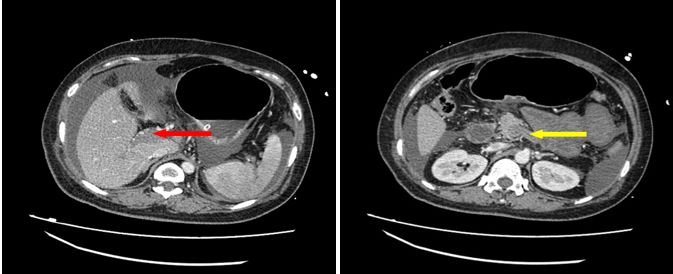

很快,腹部增强CT(见图B)和门静脉系统CTA(见图C)的结果回来了:

1.门静脉主干、右支及其属支密度减低,血栓形成可能;腹盆腔积液,小肠管壁增厚;

2.胆囊术后缺如;

3.孕期子宫;

4脂肪肝;

5.门静脉系统的广泛、完全的栓塞。

图B腹部增强CT(静脉期2018.04.15):门静脉、脾静脉未见造影剂充盈(红色箭头代表门静脉、黄色箭头代表脾静脉)

图C门静脉系统CTA(2018.04.15):门静脉、脾静脉、肠系膜上静脉未见造影剂充盈(红色箭头代表门静脉、黄色箭头代表脾静脉、绿色箭头代表肠系膜上静脉)